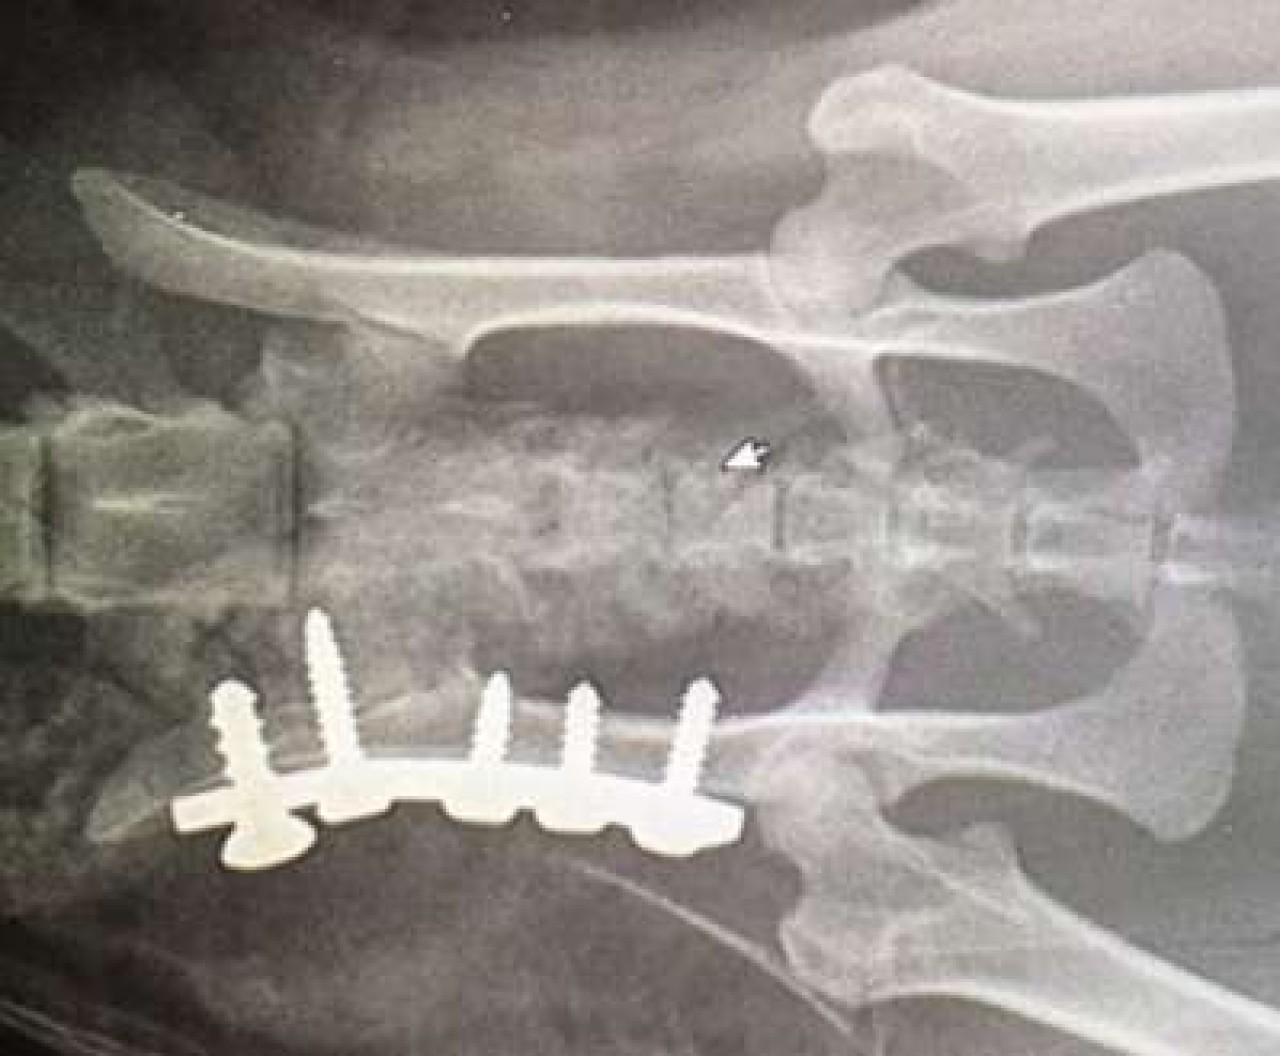

En images